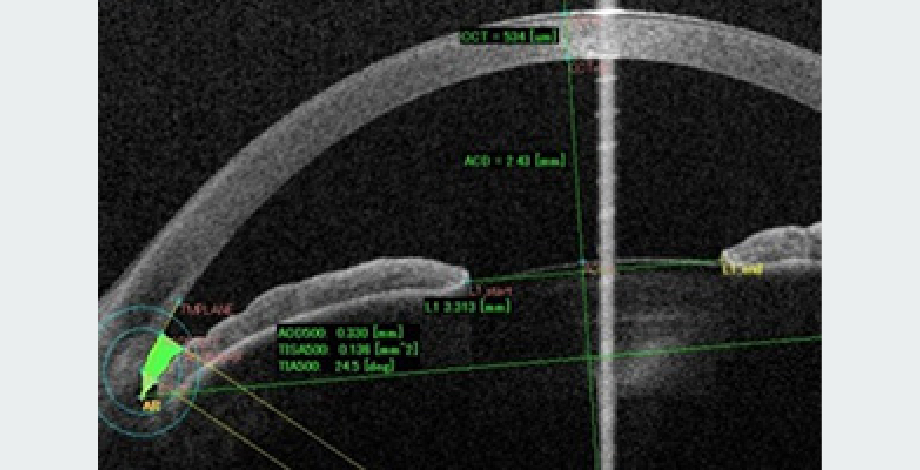

角膜診療にあたって、当院では最先端検査機械が揃っています。例えば、レーザー共焦点顕微鏡(HRT-II RCM、図1)は非侵襲的に眼表面を細胞レベルで観察することができ病態解明に大変役に立ちます。また、CASIA SS-1000前眼部光干渉断層計(AS-OCT)は角膜以外、前房、隅角、虹彩など前眼部のあらゆる組織の形態を三次元で非侵襲的に検査することができます。特に、角膜手術の際に術前、術後のフラップ厚の測定、角膜形状は表面及び裏面の評価もでき画期的な貢献を果たしています(図2)。

図2. 前眼部OCT検査

CASIA SS-1000

前房、隅角解析例